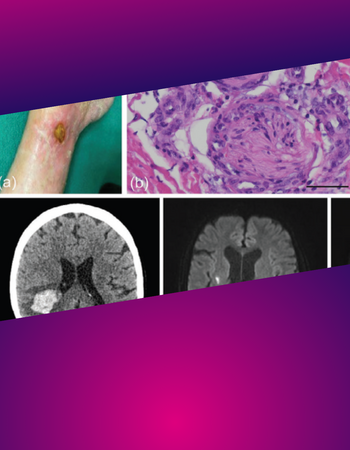

Diagnose-Quiz

Sieht man in der Ferne einen Vogel über die Kieler Bucht fliegen - was ist es wohl? Eine Möwe oder ein Kolibri? Oft liegt die Antwort scheinbar auf der Hand und das fast unmögliche wird gar nicht erst bedacht. So entpuppt sich manch harmloser Pickel erst auf den zweiten oder gar dritten Blick als echter Spezialfall. Andere Symptome sieht man einmal in zehn Jahren und kann sie deshalb evtl. nicht geich zuordnen... Unser Diagnose-Quiz fordert Dich mit ungewöhnlichen oder kniffligen Fällen heraus, die das Hirn so richtig auf Trab bringen.

Die Diagnosequizze werden uns freundlicherweise zur Verfügung gestellt vom "Journal der Deutschen Dermatologischen Gesellschaft" © Deutsche Dermatologische Gesellschaft